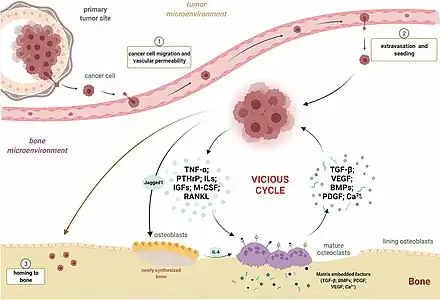

Quand des cellules cancéreuses se détachent de la tumeur primitive et circulent dans le système sanguin ou lymphatique, alors un petit nombre de ces cellules peut se fixer dans d'autres organes et s'y multiplier (« former une colonie »)[23]. Dans le cas de métastase osseuse, la dissémination se fait presque exclusivement par voie sanguine.

L'os reçoit environ 10 % du débit sanguin. On y observe pourtant plus fréquemment des métastases que dans d'autres organes plus vascularisés (comme le cerveau). Ceci s'explique principalement par la structure des vaisseaux sanguins dans l'os. Au niveau de la moelle osseuse, les capillaires sont sinusoïdes : les cellules endothéliales sont disjointes, et la membrane basale perd sa cohésion, ce qui explique que les cellules cancéreuses peuvent plus facilement sortir des vaisseaux et s'installer dans l'os.

Les organes cibles pour l'installation de cellules tumorales sont souvent ceux qui sont les plus proches de la tumeur primitive, et en aval du courant. D'habitude, les cellules cancéreuses détachées de la tumeur primitive envahissent la moelle osseuse par l'artère nourricière, l'artère apportant le sang dans l'os. Par contre, le carcinome de la prostate fait des métastases avant tout à travers un plexus veineux se trouvant devant la colonne vertébrale, et donc, par fréquence décroissante, les vertèbres lombaires, le fémur, le bassin, les vertèbres dorsales et les côtes[24].

Les domaines de l'os dans lesquels se fait l'hématopoïèse offrent aux cellules cancéreuses des conditions de croissance favorables[25]. La faible vitesse d'écoulement du sang dans l’os facilite en outre l'accrochage des cellules à la paroi du vaisseau. C'est alors que la membrane basale séparant le vaisseau et la moelle peut être ouverte par des enzymes de la cellule tumorale et cette dernière peut pénétrer dans la moelle[26]. Les métastases osseuses naissent presque exclusivement dans le volume de la moelle[27].

Au début, la métastase se trouve dans la cavité remplie de moelle rouge à l'intérieur de l’os. Puis des régions plus éloignées de l'os spongieux, et enfin l'os compact sont attaqués[2],[28]. Les cellules cancéreuses perturbent l'homéostasie osseuse qui est basée sur l'équilibre entre la formation osseuse et la résorption osseuse. L'hyperactivité ostéclastique aboutit à des métastases ostéolytiques.L'hyperactivité ostéblastique aboutit à des métastases ostéocondensantes

La question de savoir quels sont les organes préférés par les cellules cancéreuses pour faire des métastases n'a pas encore reçu de réponse dans une large mesure[23] ; selon la théorie seed-and-soil, la colonisation a lieu quand la cellule tumorale (seed) montre une affinité particulière pour le milieu environnant l'organe concerné (soil)[7]. Les protéines avec de bonnes propriétés d'adhésion, comme les cadhérines, semblent jouer un rôle important pour la colonisation.

Métastases ostéolytiques, ostéocondensantes et mixtes

Dans les os, les cellules tumorales provoquent des modifications locales de la structure de l'os, qui sont amenées par une perturbation de l’équilibre, dans le remodelage du tissu osseux. Celles-ci peuvent être soit ostéocondensantes (formant de l’os) soit ostéolytiques (détruisant de l’os), ou mixtes ostéocondensantes/ostéolytiques. En outre, les métastases osseuses peuvent libérer diverses hormones qui conduisent à une ostéopénie dans l'ensemble du squelette[32]. Les cellules des métastases osseuses ne prennent en général pas part directement à la formation ou à la destruction de l'os. Ces processus sont provoqués par les ostéoblastes et les ostéoclastes, cellules compétentes pour la formation et la destruction de l'os durant le remodelage du tissu osseux : elles sont mises en jeu par des protéines de signalisation émises par les cellules tumorales[6]. Dans de rares cas, et seulement pour des métastases très agressives, il y a une destruction directe de la matrice osseuse par les cellules tumorales, qui produisent des enzymes lytiques, comme des hydrolases lysosomales, des peptidases ou des collagénases[2],[33].

Interaction entre cellule cancéreuse et os

L'apparition d'une métastase dans les os n'est pas un processus aléatoire, mais le résultat d'interactions moléculaires complexes entre les cellules cancéreuses détachées et leur environnement : ces interactions permettent aux cellules tumorales de pénétrer dans la matrice extracellulaire de l’os et d'y proliférer dans l'os.